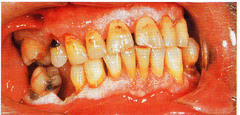

Meth mouth

-generalized extensive destruction of tooth surface -meth use